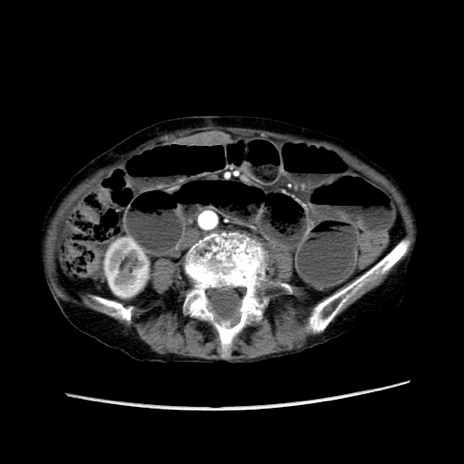

冠状断像

【症例】80歳代女性

【主訴】胸のつかえ感

【現病歴】約9時間前に食後から胸のつかえた感じあり、嘔吐あり、来院。

【既往歴】胃癌(全摘)、胆摘、虫垂炎

【身体所見】心窩部に圧痛あり、反跳痛なし。

【データ】WBC 5700、CRP 0.05